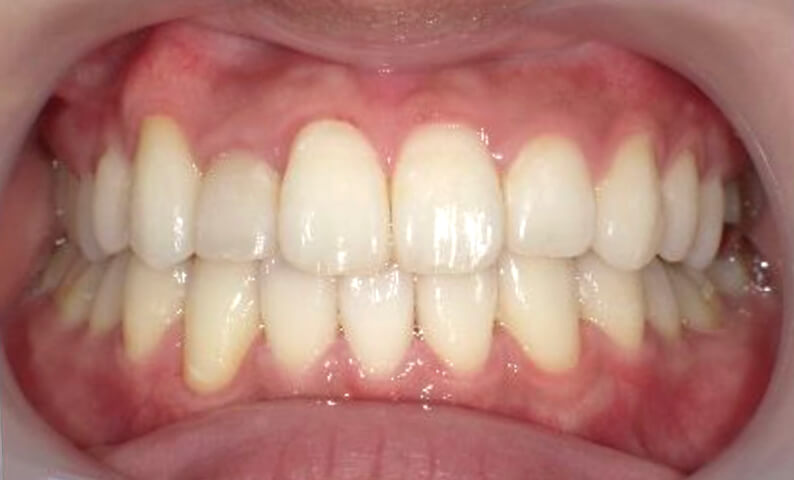

症例_023 上顎だけの部分矯正

治療期間:9ヶ月金額:30万円+税女性前歯のガタガタ上の前歯だけ

| Before | After |

|---|---|

|